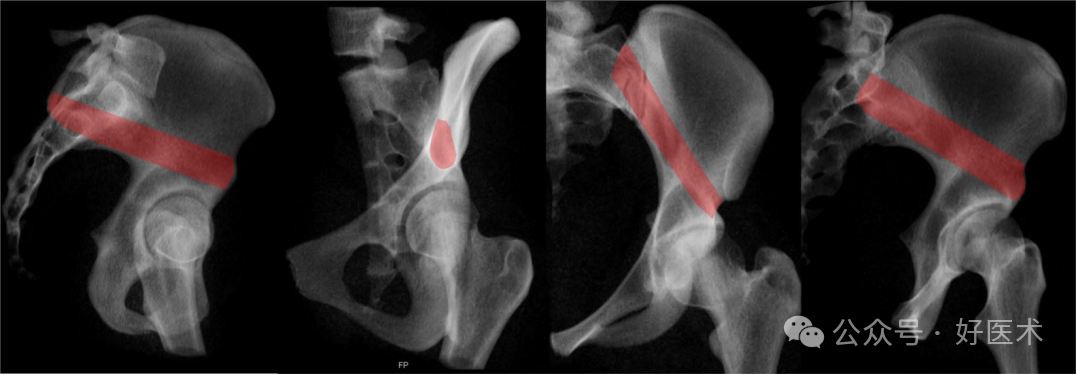

COOO通过创建一个泪滴图像(图7,红点区域),可以看到从AIIS到PSIS的髋臼上通道的轴向方向。此外,可以观察到上支的全长,以便应用前柱螺钉或逆行上支螺钉。在临床上,骨性通道的三维形状以二维形式可视化。影像增强器通常向患侧旋转45°(OOV),向尾侧旋转40–50°(POV)(图7)。

图7 闭孔出口视图(COOO)。透视机向尾侧旋转50°,并向患侧旋转45°。

图 17 使用真侧位视图、COOO、骨盆入口和 CIOO 视图(从左到右)对髋臼上通道 (SAC) 进行放射成像观察。

对于SAC,建议所有可能的标准视图及其组合,包括标准PAP、OOV、IOV、COOO、PIV、TLV、COOI和CIOO。最相关的视图是髂骨外侧外斜位(COOO),在这个视图中,通道呈现出泪滴形状。泪滴形状的下部应**位置于直接与髋臼顶(sourcil)相切的位置,且泪滴形状应尽可能小,以便**地确定螺钉的入口点。在插入螺钉时,应考虑关节囊附着点可延伸至髋臼顶(sourcil)上方16毫米处。经典的髂骨外侧斜位(IOV)确认螺钉放置在大坐骨切迹上方的**位置。为了术中分析螺钉路径,建议采用多种视图(图17):

TLV(髂骨斜位):确认螺钉位于大坐骨切迹上方。

COOO(髂骨外侧外斜位):分析从骶骨后上棘(PSIS)到髂前下棘(AIIS)的骨通道内螺钉的轴向方向(起始点);可以排除螺钉的内侧或外侧穿透。

PIV(髂骨内侧斜位):确认螺钉路径位于骶髂关节的外侧。

IOV(髂骨外侧斜位):确认螺钉路径位于大坐骨切迹上方,并分析螺钉长度。

COOI(髂骨外侧内斜位):分析髂骨的外侧和内侧边界。

建议采用的视图有 COOO、COOI 和 IOV 以及将植入物插入 SAC 的 TLV。